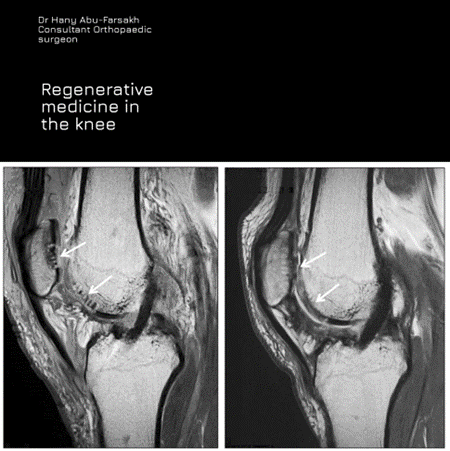

Now, in a multidisciplinary approach, hundreds of UK patients are taking part in unique medical trials. The results to date are very promising. The idea was a collaboration between scientist Professor Richard Webb, and Jordanian Dr. Hany Abu Farsakh, a specialist in regenerative medicine and reconstruction surgery.

The research included 179 patients from south-east London, who were suffering knee osteoarthritis and booked for total knee surgery with a waiting period of more than 90 days. Dr.Abu-Farsakh said: “This is a breakthrough when we consider the difficulty of treating joints with severe osteoarthritis without replacement surgery. Treating these advanced cases with intra-articular injections was not even an option.”

These ‘day-case’ outpatient injections form part of a 6-week treatment protocol, and patients will be monitored for five years before full results are published. Satisfaction rates are impressive at 90%, and two thirds of the patients decided to be taken off the operation list. The stem-cell knee injections are followed by 6-weeks of carefully tailored dietary and lifestyle changes, supplements and physiotherapy.